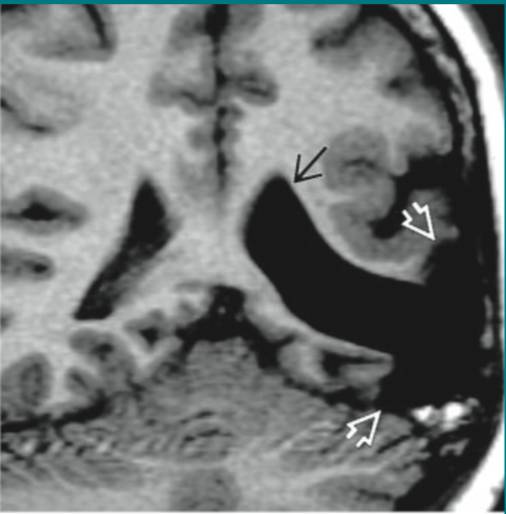

皮样囊肿破裂